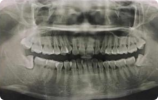

题目:患者,男,38 岁。上前牙变色 1 年,自述上前牙 5 年前受过外伤,唇侧倾斜,检查可见左上 1 牙冠变色,牙冠缺损近 1/2,牙髓测试无反应,X 线根尖片显示患牙无明显异常,全景片显示双侧下颌智齿近中阻生,之前有发炎化脓病史,目前无咀嚼不适。口腔其余无异常。检查情况及X线片见下图:

1.主诉诊断:左上 1 牙髓坏死(外伤)

非主诉诊断:双侧下颌智齿冠周炎(近中阻生)

2.主诉疾病诊断依据:(1)上前牙变色 1 年,上前牙 5 年前受过外伤,唇倾明显。(2)检查见左上 1 牙冠变色,牙髓测试无反应,牙冠缺损近 1/2,X 线片无明显异常。

非主诉疾病诊断依据:X 线全景片显示双侧下颌智齿近中阻生